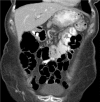

Case presentation: An 84-year-old woman of Caucasian background presented with 12 months of worsening abdominal pain, nausea, vomiting, diarrhea and weight loss on a background of known gastric ulcer disease.

Conclusion: The leading cause of gastro-colic fistulae has changed from benign to malignant due to improved medical management of gastric ulcer disease. The rarity and non-specific symptoms of gastro-colic fistula make the diagnosis difficult and it is best made by barium enema; however, computed tomography has not been formally evaluated. Surgical management with en bloc resection of the fistula tract is the preferred treatment. Benign gastro-colic fistulae are becoming exceedingly rare in the context of modern medical management of gastric ulcer disease. Surgical management is the gold standard for both benign and malignant disease.